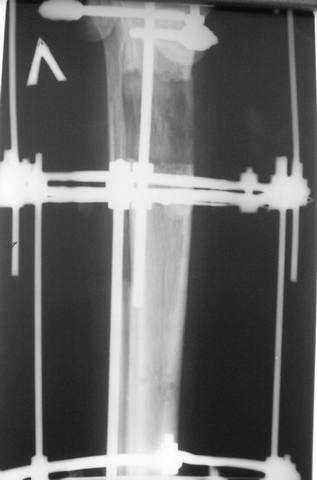

Реализовал описанную выше методику, и в итоге вот что получилось. Высылаю лишь прямые проекции,

в боковых тоже всё в тему.

Очень пригодились карбоновые кольца (Джолдас -огромное спасибо, я твой должник!!!), поскольку остеопороз дистального отломка был просто невероятный. На цифровом рентгене с трудом угадывались контуры.

Рентген в процессе перемещения - внизу карбоновые кольца, тракция фрагмента спицами с упором.

внешний вид в аппарате - не завершающем этапе, сначала стопа тоже была фиксирована в аппарате.